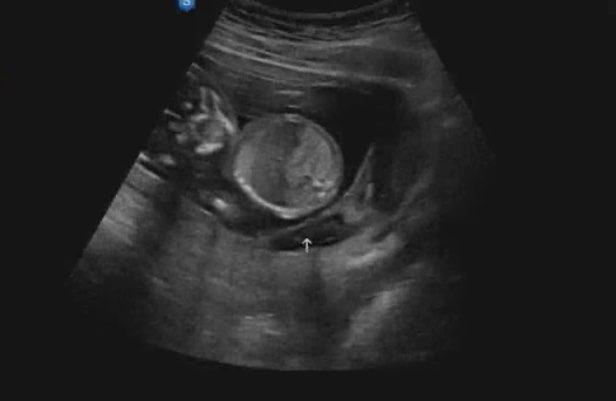

접수를 하고 진료실 앞에서 대기를 한다. 예약한 시간을 조금 넘겨서 아내의 이름이 불려져 믿음직한 의사 선생님 앞에 조심스레 앉았다. 그리고 초음파실에 들어갔다. 이내 딱 봐도 차가울 초음파 젤이 뜨거운 아내 배 위에 떨어진다. 내 배도 아닌데 시리다. 그리고 의사 선생님은 능숙하게 초음파로 배 위를 훑는다. 우리의 눈은 모니터에 집중하고 귀는 좋은 말을 들을 준비가 되어있다. 드랍 더 좋은 말. 빠르게 움직이는 초음파 화면에서 예쁨이의 모습을 확인하기가 쉽지 않았다. 지금까지의 초음파는 아이의 모습을 부모에게 보여주기 위한 뷰 서비스처럼 느껴졌다면 오늘의 초음파는 아이의 상태를 빠르게 확인하기 위한 의사선생님 위주의 철저한 검사 목적처럼 보였다. 다음 환자들이 줄 대기를 하고 있는 상황도 한몫했을 것이다. 하지만 우리 선생님에겐 대충은 없다.

어느 정도 상태를 파악하신 후 조금씩 초음파의 속도를 늦춰가며 입을 떼신다. 염려가 많았던 양수의 양은 계속 적당한 수준으로 매우 좋다고 하신다. 물 먹기의 승리다. 이어 머리의 길이를 재며 뼈 모양을 확인시켜 주시고, 다리의 뼈와 길이도 체크하시면서 예쁨이가 주수에 맞게 건강하게 자라고 있다고 말씀하신다. 키와 몸무게도 알려주시며 다 좋다고 말씀하신다. 아내와 내 삶에서 가장 기쁨이 되고 안도가 되는 반가운 소리이다. 이제 예쁨이는 모든 장기들이 생겨나 발달하고 있고 갈비와 팔다리 등에 뼈도 잘 생겨났다. 초음파를 보면 마치 엑스레이처럼 뼈가 하얗게 보인다. 이 작은 아이의 몸에 모든 게 있다.

허벅지는 아빠를 닮아 벌써 튼튼해 보이고 하체가 발 끝까지 아름답게 쭉쭉 뻗은 것은 엄마를 닮았다. 점과 같은 모습으로 심장만 반짝이던 예쁨이가 어느새 이렇게 진짜 사람의 모습으로 컸다니.. 예쁨이가 진짜 사람이 맞지만 진짜 사람처럼 성장하는 게 신기하기만 하다.

보통 16주는 성별을 확인하는 주수이기 때문에 많은 이들이 이때를 특별히 더 기대한다. 하지만 효자 예쁨이는 14주에 훌륭한 '남아'라며 스스로 분명하게 알려주었다. 그러니 성별 반전 같은 건 없었다. 반박할 여지가 없었기 때문에 반전을 생각하지도 않았다.